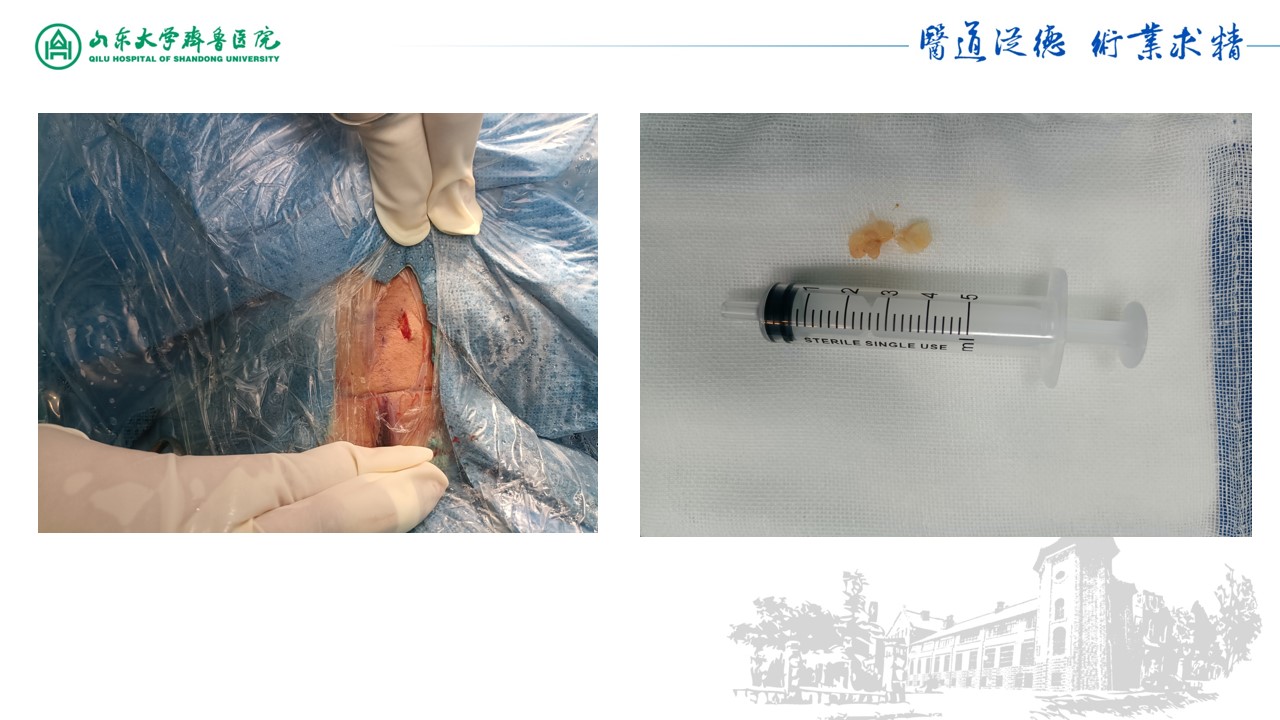

05-取出第一块髓核

06-取出第二块髓核